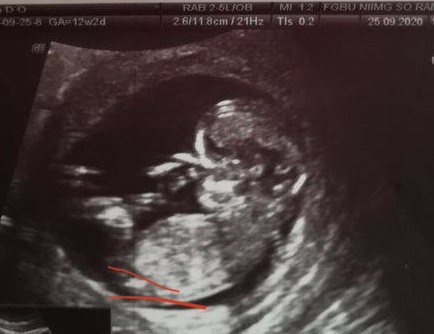

Если то что я вижу на последнем снимке это половой бугорок, то это мальчик, ну и по форме головы тоже можно предположить мальчика 🤗

Катя, мне кажется половой бугорок тут между ножек, серого цвета) белым на узи кости подсвечиваются) я очень сильно чувствую девочку, думала все предположения тоже о девочке будут 😄

Как раз угол что вы нарисовали девчачий. Такчто мой вердикт "диванного эксперта"- девочка). Автору удачи и главное здорового малыша.

вот так торчит у мальчиков.